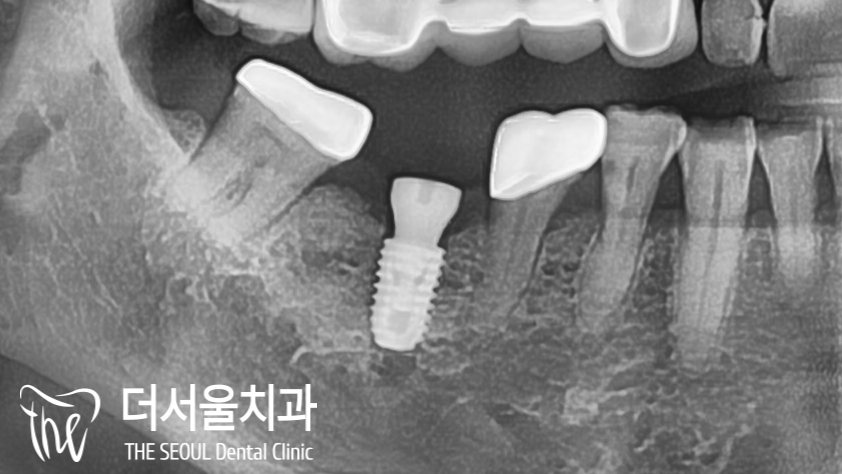

『디지털 임플란트 한 번 더! 심어드렸음』

반대쪽도 브릿지가 있었습니다.

똑같이 치아가 없는 곳은

디지털 임플란트 로,

있는 곳은 다시 제작을 하기로 했습니다.